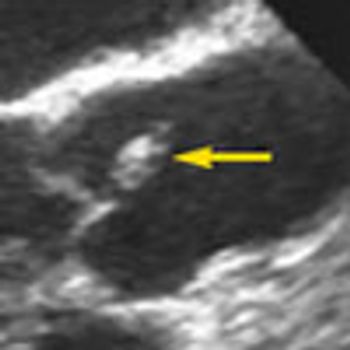

A 38-year-old man with a history of alcoholism, intravenous drug use, and cerebrovascular accident was referred for assessment of possible endocarditis, based on history, fever 39 °C (102.9 °F) and mildly elevated troponin level.